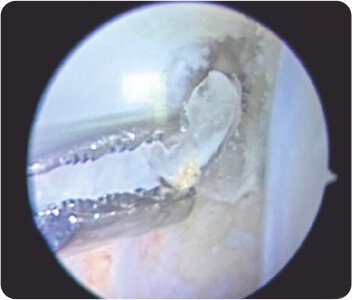

Lax Anterior cruciate ligament graft

Broken screw

X-ray showed no fractures. The Femoral tunnel was noted to be in an abnormal position. MRI showed complete ACL and medial meniscus posterior horn tears. The patient was planned for revision arthroscopic anatomic ACL reconstruction +/- medial meniscus surgery. During arthroscopy, significant laxity of the ACL and partial tear of posterior horn of medial meniscus were noted. The hamstring graft was harvested from the contralateral knee, as the ipsilateral graft was harvested during the index surgery. The graft was augmented with FiberWire for internal bracing. Old ACL remnants were cleared with a shaver. Loose pieces of old femoral BioScrew were removed. Partial medial meniscectomy was done and trimmed to stable borders. New femoral and tibial tunnels were made. Anatomic ACL Reconstruction was done and stabilised with Arthrex Tightrope RT on femoral side and BioComposite screw on tibial side. Final stability showed negative anterior drawer test. The next day, he was mobilised with full weight-bearing walking. On follow-up, he achieved full range of movements and returned to normal sporting activities.